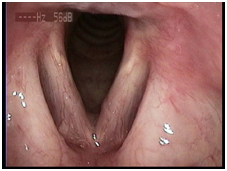

1、 动态喉镜:可在高清模式下动态观察声带黏膜波振动、声门关闭等情况,该检查能精确量化声带病变的范围与程度,视频资料便于保存可用于治疗前后的疗效对比。

声带息肉术前 声带息肉术后

声带麻痹术前 声带麻痹术后